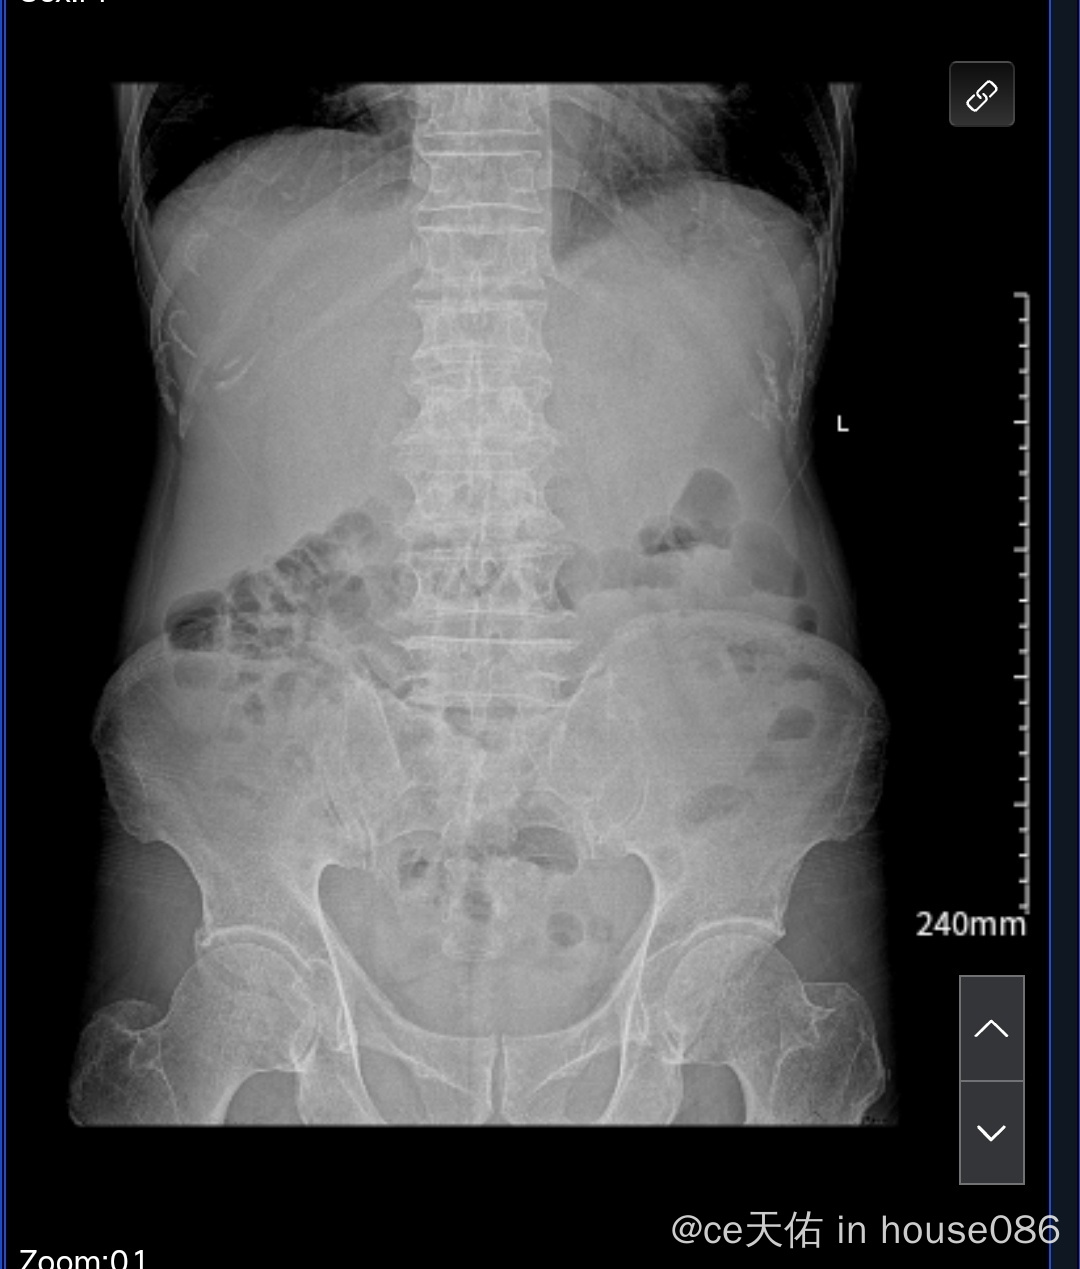

吃了六天来那度胺,中途第三四天感觉脾脏部位开始有点不舒服,第六天去检查后停了来那度胺,开始打升白针特比奥,后面输促肝细胞生长素/谷胱甘肽/酚磺乙胺/美罗培南/地塞米松,后面肚子胀去拍平片说不完全肠梗阻,上胃管打油和灌肠,现在几天下来还是肚子胀,请大神看看是不是淋巴转移脾脏了?